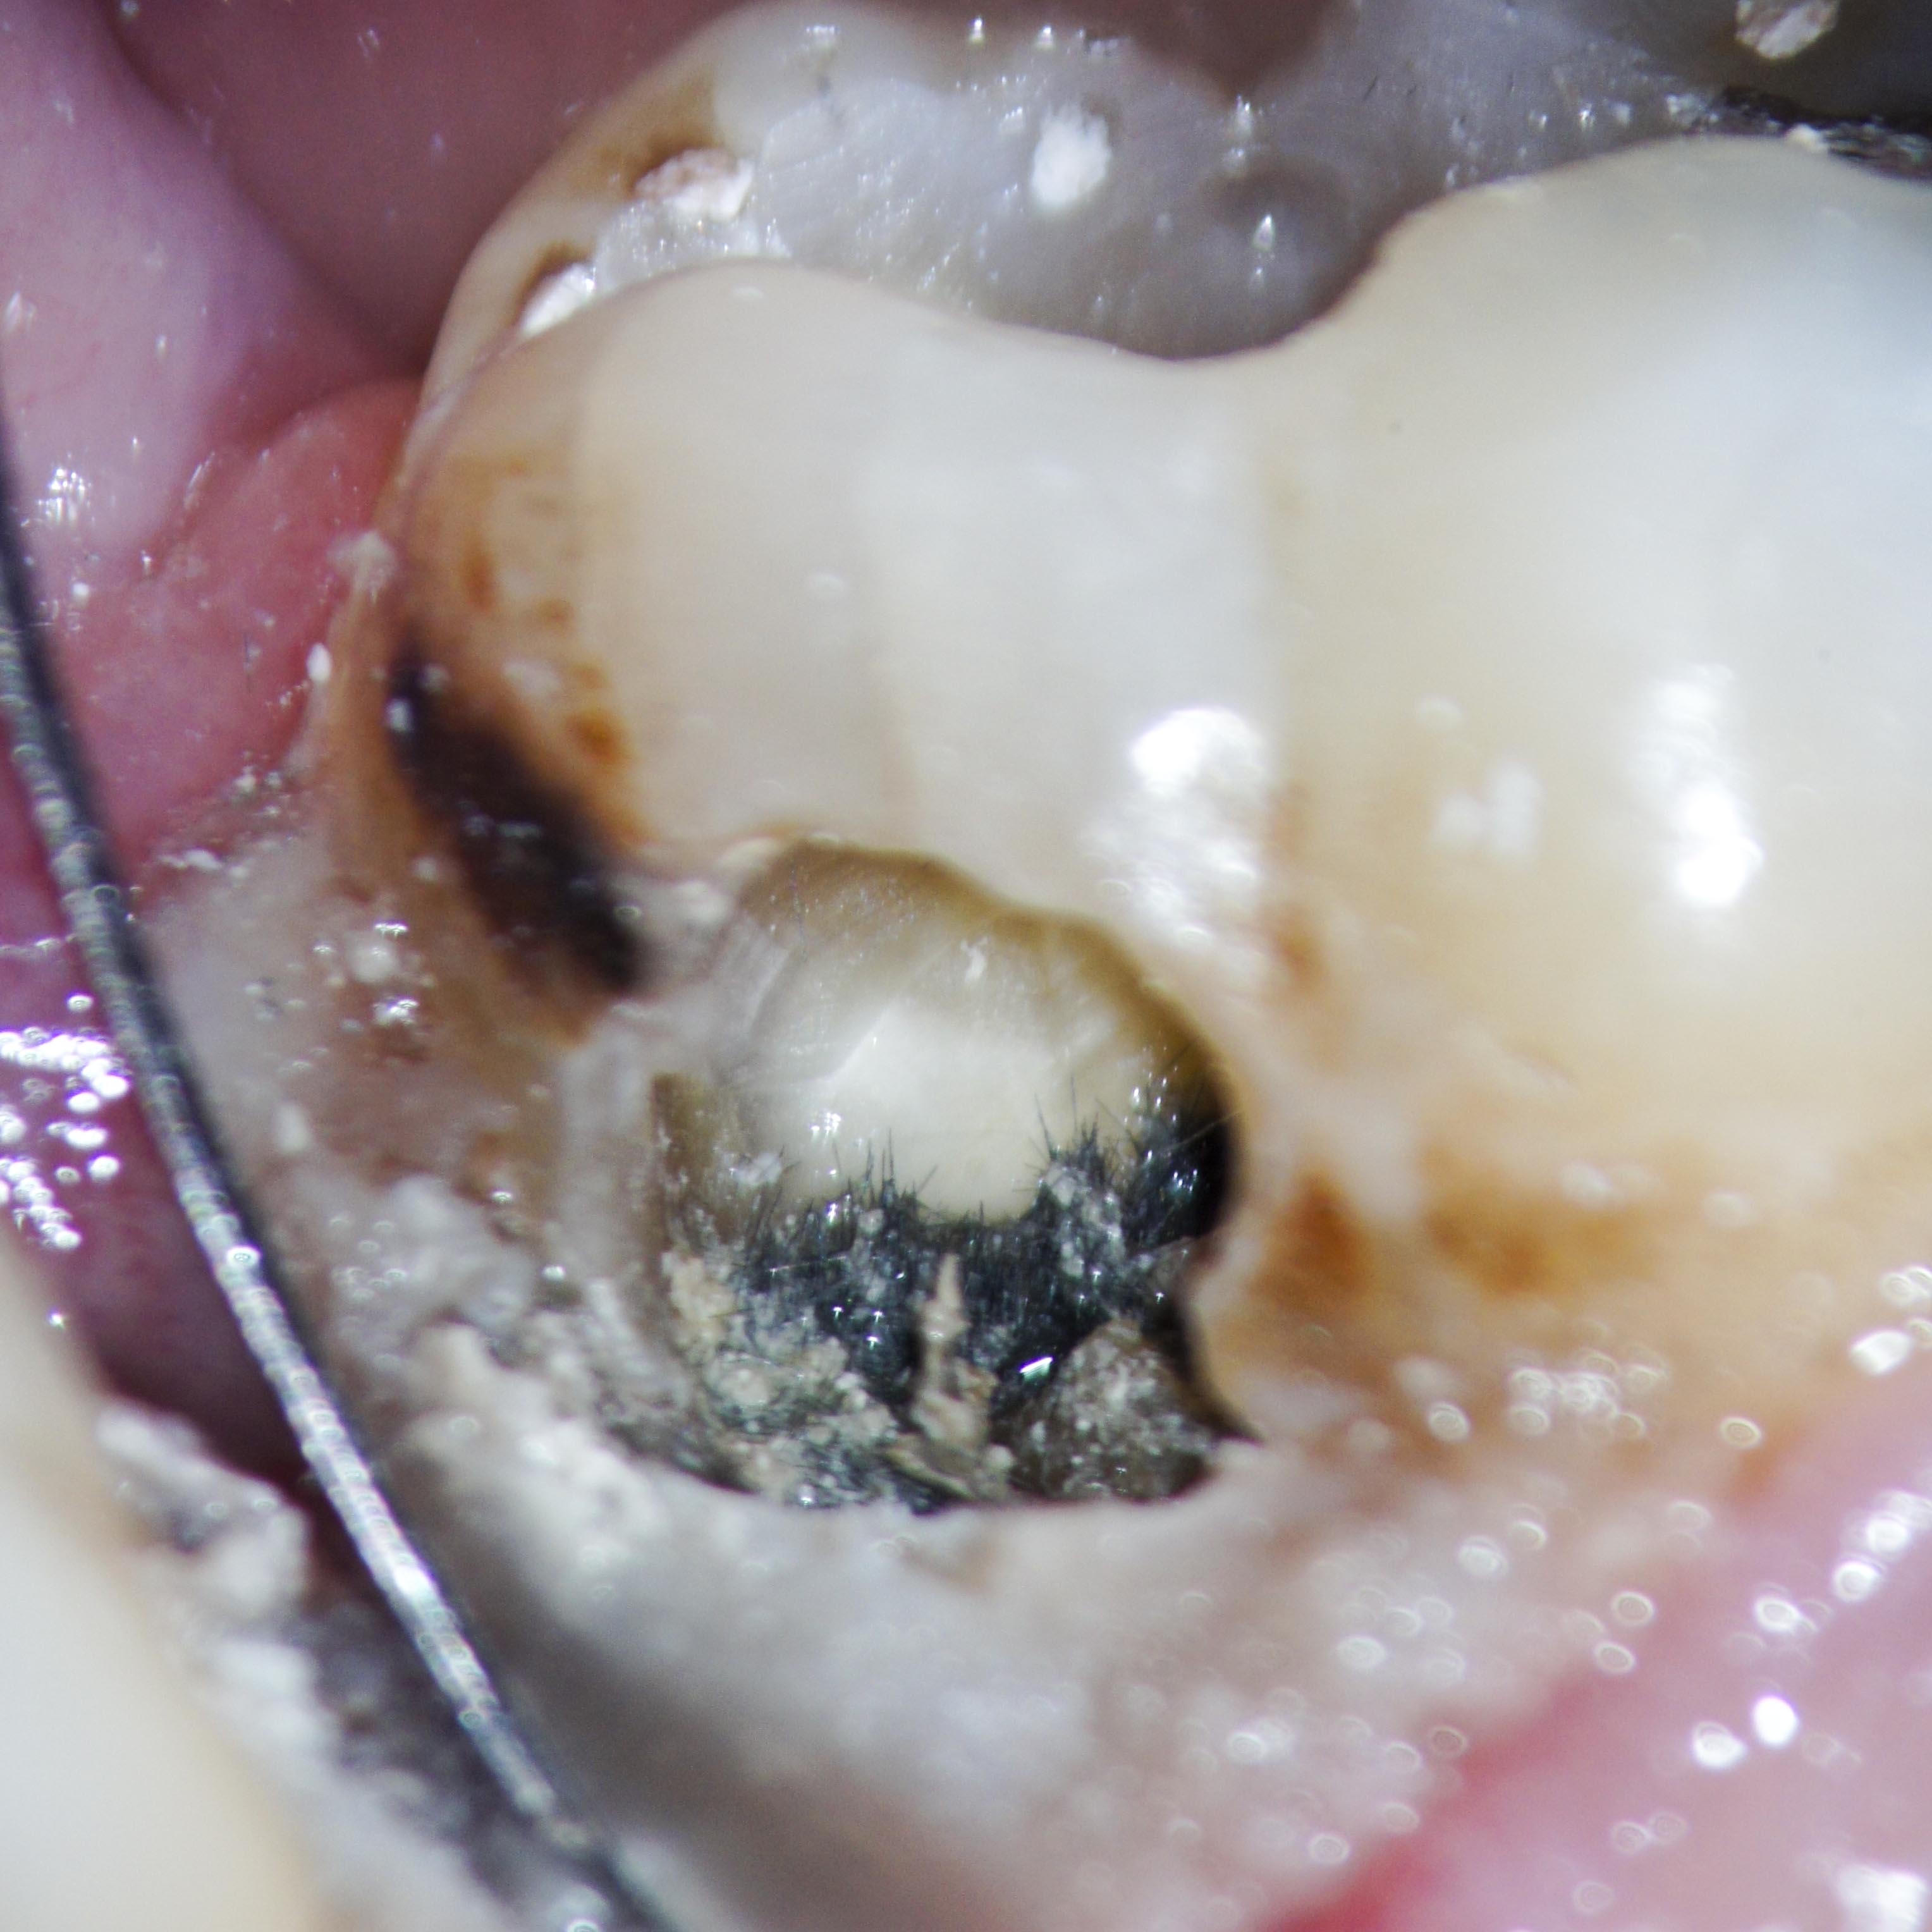

Gingivanekrose nach medikamentöser Einlage